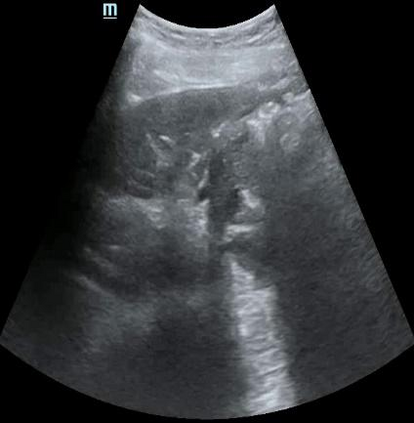

Most deep neural networks (DNNs) based ultrasound (US) medical image analysis models use pretrained backbones (e.g., ImageNet) for better model generalization. However, the domain gap between natural and medical images causes an inevitable performance bottleneck. To alleviate this problem, an US dataset named US-4 is constructed for direct pretraining on the same domain. It contains over 23,000 images from four US video sub-datasets. To learn robust features from US-4, we propose an US semi-supervised contrastive learning method, named USCL, for pretraining. In order to avoid high similarities between negative pairs as well as mine abundant visual features from limited US videos, USCL adopts a sample pair generation method to enrich the feature involved in a single step of contrastive optimization. Extensive experiments on several downstream tasks show the superiority of USCL pretraining against ImageNet pretraining and other state-of-the-art (SOTA) pretraining approaches. In particular, USCL pretrained backbone achieves fine-tuning accuracy of over 94% on POCUS dataset, which is 10% higher than 84% of the ImageNet pretrained model. The source codes of this work are available at https://github.com/983632847/USCL.